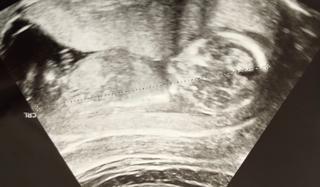

写真:14w1d:ぐぐさん

CRL87.1㍉ BPD27.8㍉

妊婦健診2回目で経腹エコーになりました。

背骨や顎などがわかるようになり、成長を感じて嬉しくなりました!

動いてる姿や性器は見られなかったので、次回に期待しています。